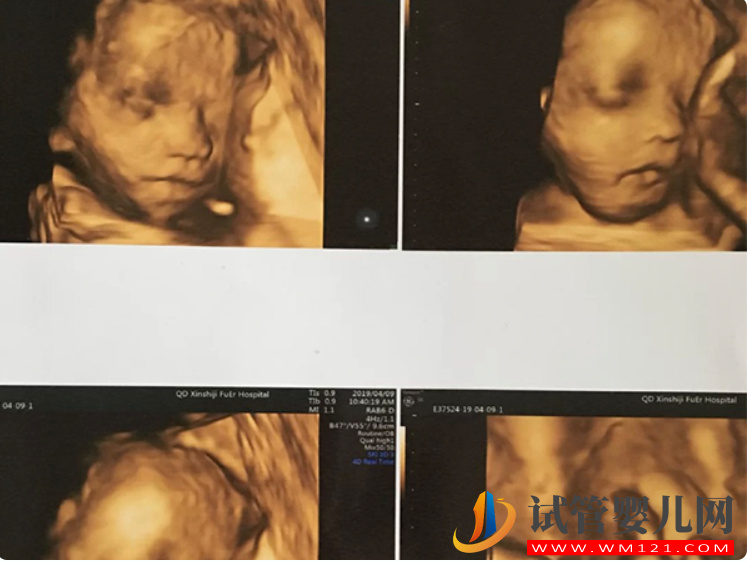

四維單子是超聲檢查的一種,除了一般彩超的功能外,還可以進(jìn)行胎兒頭面部立體成像,可清晰地顯示眼、鼻、口、下頷等狀態(tài),可協(xié)助醫(yī)生直接對胎兒先天畸形進(jìn)行診斷,包括表面畸形、內(nèi)臟畸形和頭面部畸形,能確定胎兒在子宮中的精確位置。此外四維彩超還在這些功能的基礎(chǔ)上加上時間維度參數(shù),可以實時觀察胎兒動態(tài)的活動圖像。

四維彩超單子必須是照到胎兒寶寶的全身,所以下半身也必將照到。如果彩超圖像有三條線的標(biāo)志,那是非常明顯的女性特征,生女寶寶的可能性就比較大;如果彩超圖像有突出的像一團(tuán)菌狀的物體,那正是男性特有的標(biāo)志,則生男寶寶的可能性比較大。